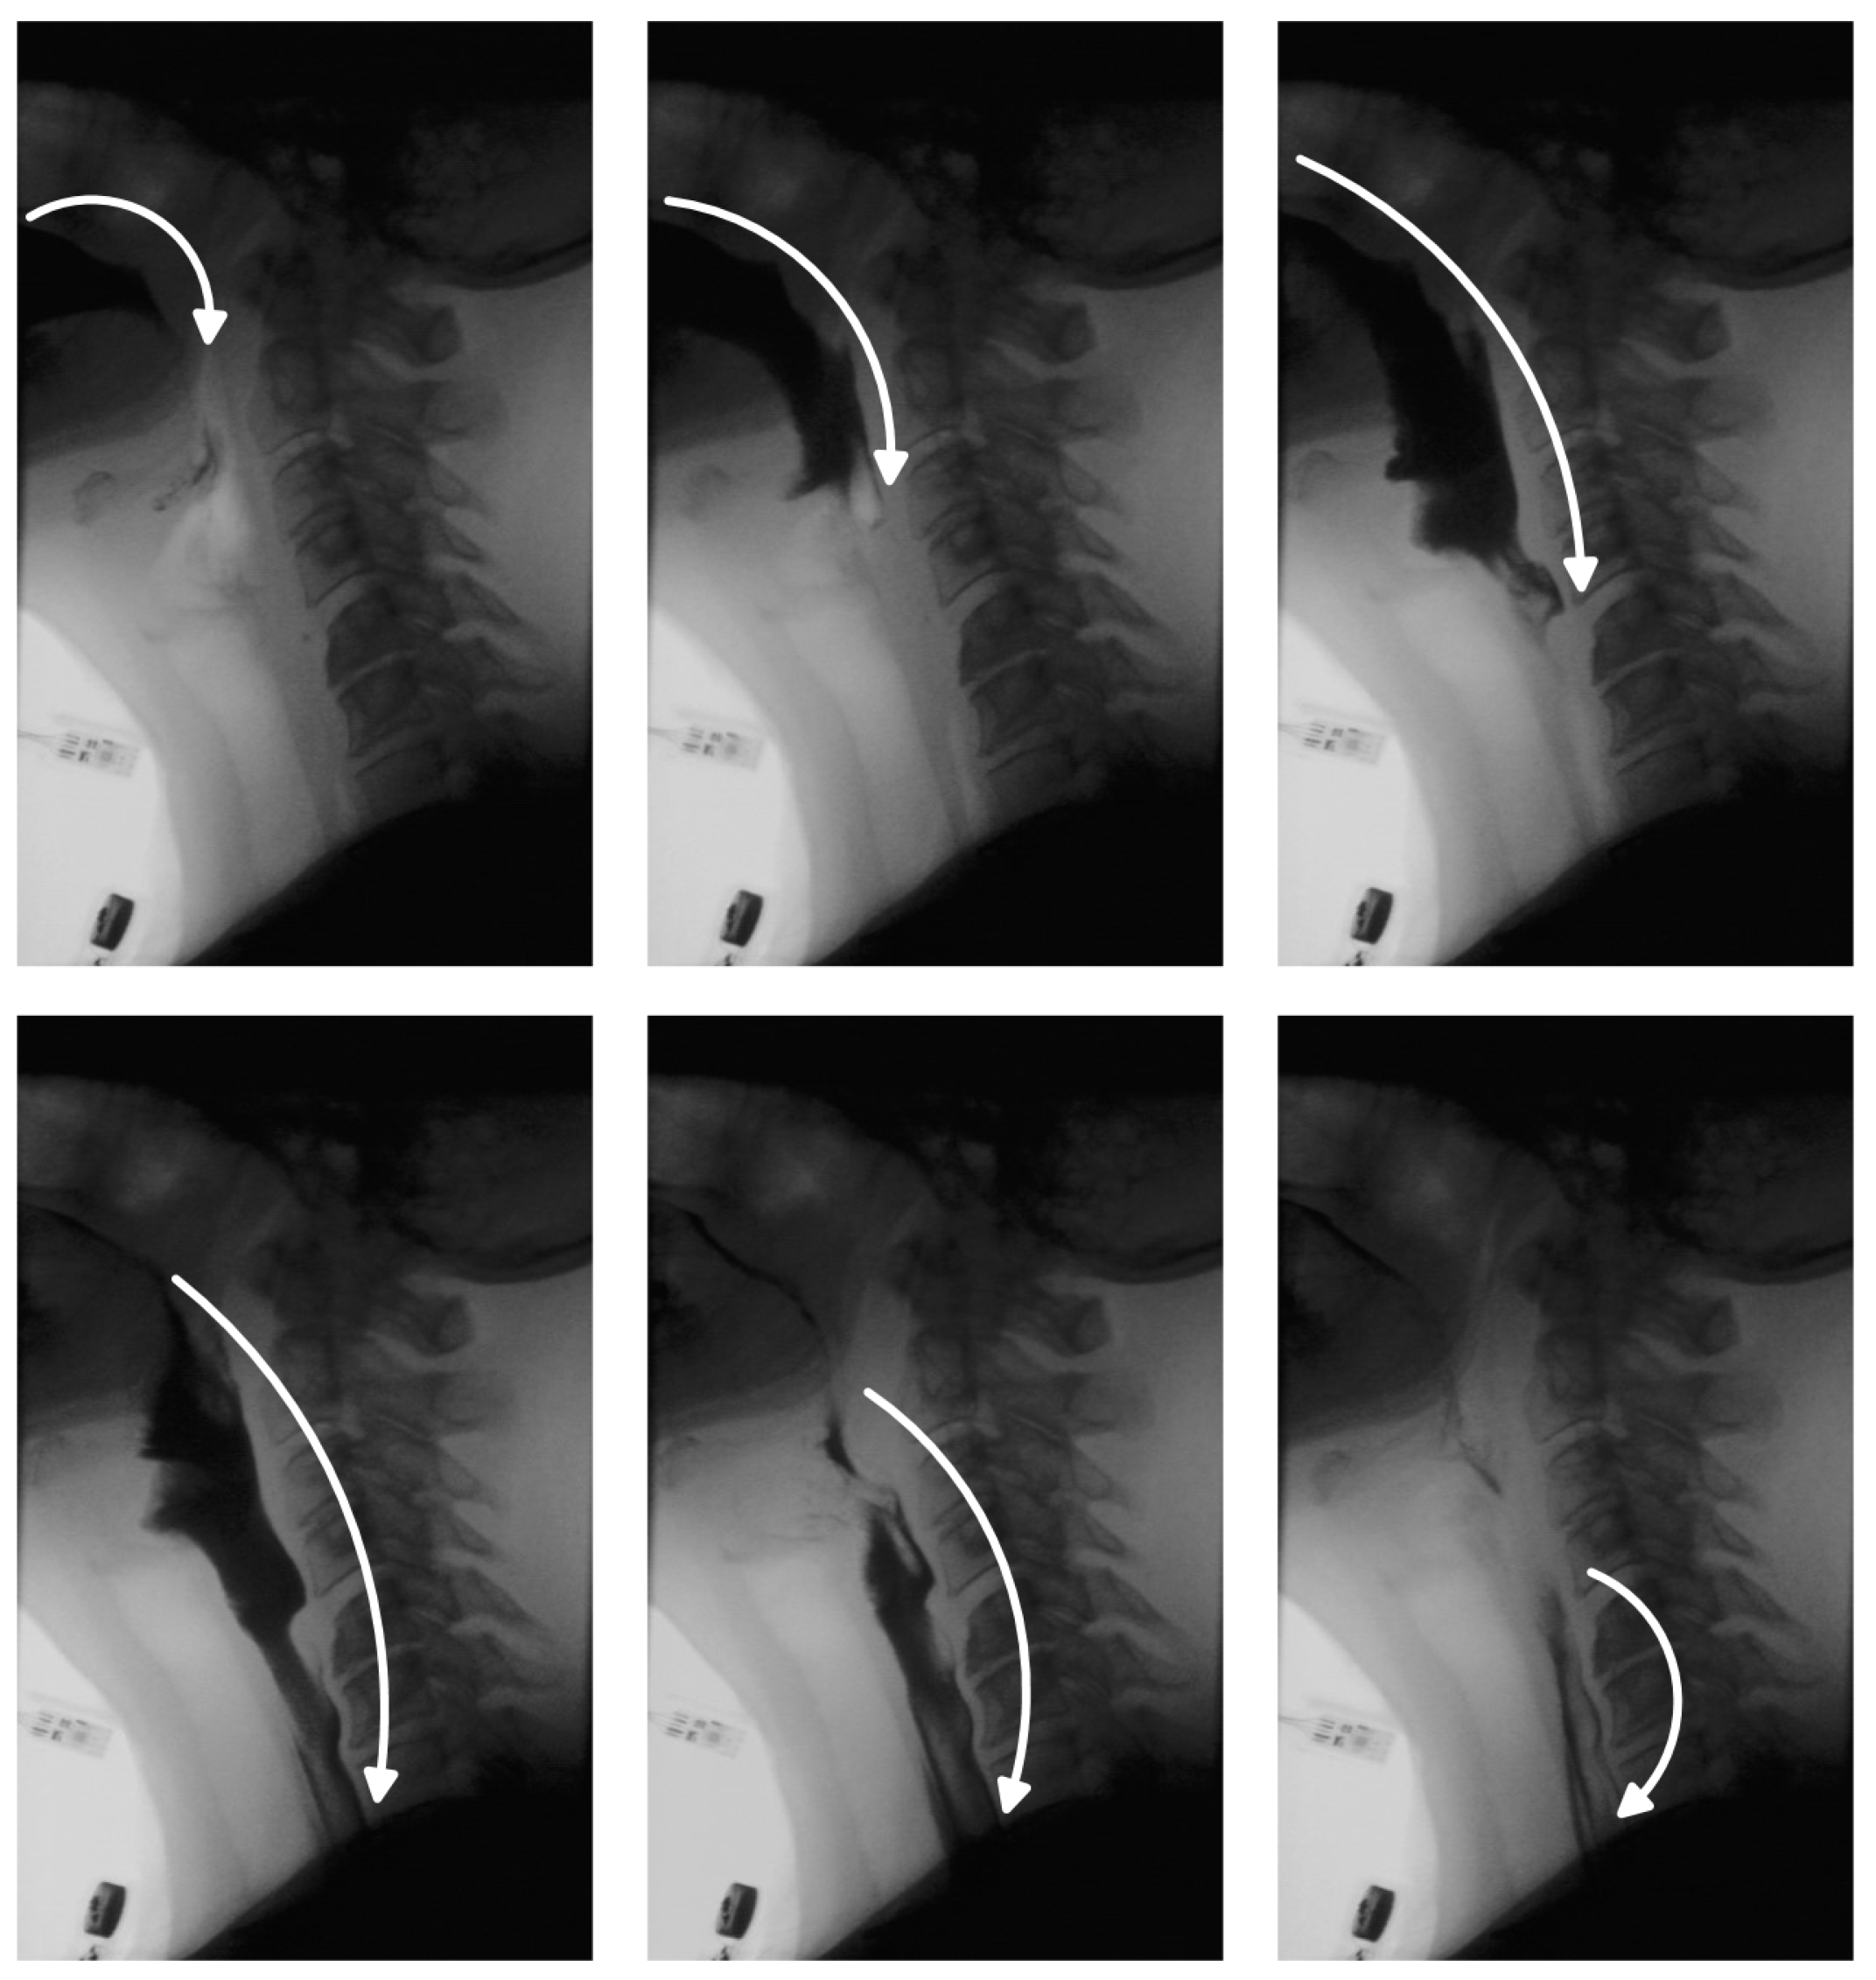

Figure 5 focuses on bolus residue segmentation, showcasing output masks generated by our unsupervised model. The last column also includes results from the supervised model [14] applied to the residue detection task. Although supervised models perform well in bolus tracking, they often struggle with residue detection. These models are typically trained on frames containing well-defined bolus structures, making them less effective at identifying residue, which tends to be smaller, lower in contrast, and more spatially dispersed. As a result, supervised models often fail to generalize, overfitting to the visual characteristics of the bolus and missing the subtle, irregular appearance of residue regions.

In contrast, our unsupervised approach does not rely on explicit object annotations. It learns inherent structural patterns from the data itself, without being constrained by predefined labels. This allows the model to remain sensitive to anomalies—enabling detection of both bolus and bolus residue—while maintaining robustness to normal anatomical variability observed during the swallowing process. Statistical testing confirms that, for residue detection, our method significantly outperforms the state-of-the-art supervised baseline in IoU and DSC metrics ( p < 0.05 , paired t-test; results for the supervised model are detailed in the next subsection).

Figure 5. Performance of the proposed model with positional encoding for bolus residue segmentation. Each row shows a sample test frame, the corresponding residue segmentation produced by our model, and the output from the supervised model [14]. (a) illustrates a case with discontinuous bolus residue, while (b,c) depict frames containing a single residue region.